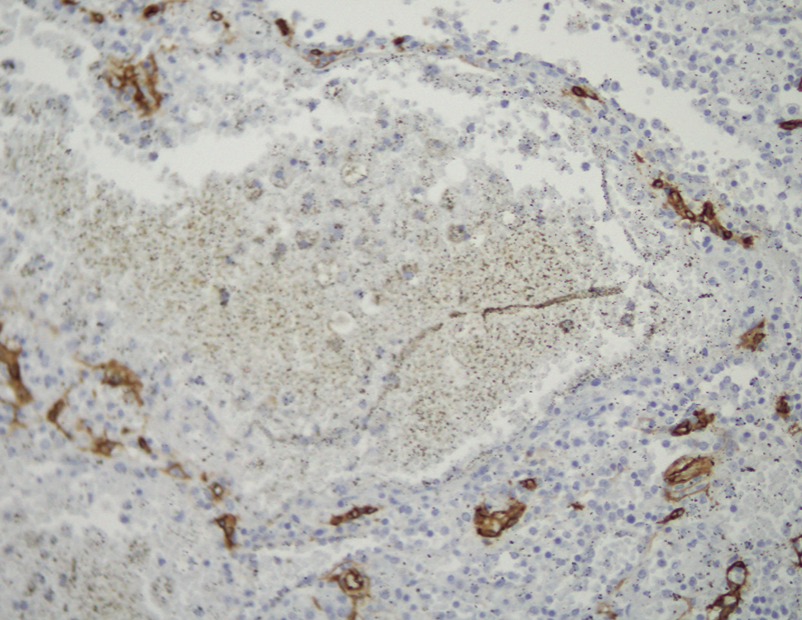

Imágenes y Cirugía

Beatriz Remezal Serrano, Mónica Patricia Rey Riveiro, Pilar Serrano Paz